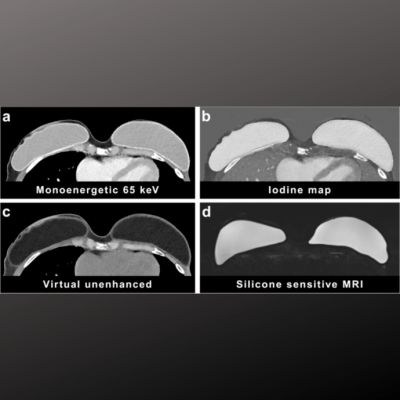

Image credit: Dr. Keith Thulborn, UIC

Image credit: Dr. Keith Thulborn, UIC